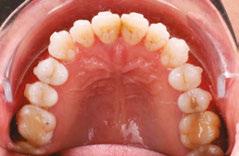

A visual screening tool validation study has recently been concluded and submitted to the Journal of Evidence-Based Dental Practice. This study is the collaboration of this author and the principal investigator Judith Owens, MD, funded by a grant from the American Academy of Craniofacial Pain (AACP). This study looked at the risk factors for pediatric sleep-disordered breathing (SDB) and craniofacial features, validated using the PSQ and a 22-item parent reported measure for SDB risk in children. Subject characteristics included age, sex, race, and ethnicity. Various craniofacial features were evaluated, such as: retrognathic mandible, open mouth posture, convex profile, midface deficiency, flat cheeks, concave profile, dolichocephalic face, frontal asymmetry, forward head posture, and rolled shoulders. It also included intraoral evaluation of: crowding of teeth, crossbite, narrow vaulted palate, crowding of upper teeth, narrow

palate, open bite, tongue thrust, crowding of lower teeth, narrow lower jaw, tongue tie, and “heart”-shaped tip of tongue. Twelve data collection sites across the U.S. were sourced to demonstrate ease of use, reproducibility, and which conditions had highest correlation. It was found that the following conditions had the highest correlation in decreasing order: forward head posture, narrow vaulted palate, open bite, tongue thrust, tongue tie, and heart-shaped tongue.